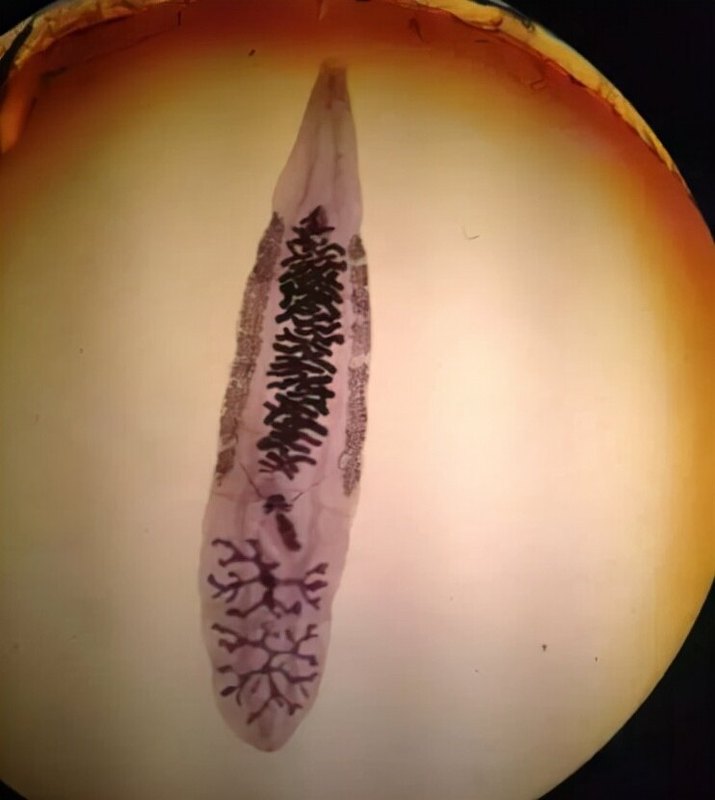

第十一節(jié)絳蟲病絳蟲病是由豬絳蟲或牛絳蟲寄生在人體小腸所引起的疾病;古代醫(yī)籍將絳蟲稱為白蟲或寸白蟲。絳蟲病在我國分布較廣。飲食習(xí)慣是決定腸絳蟲病多寡及其種類不同的關(guān)鍵因素,喜食生肉的地區(qū)感染率高。·中醫(yī)對絳蟲的形態(tài)、感染途徑很早即有明確的認識,并尋找到效果良好的治療藥物。在感染途徑方面,早在《金匱要略·禽獸魚蟲禁忌并治》篇即指出:“食生肉,飽飲乳,變成白蟲?!薄吨T病源候論·寸白蟲候》說:“以桑枝貫牛肉炙食”噲引起本病。而對于絳蟲形態(tài)的描述,《諸病源候論·寸白蟲候》說:“寸白者,九蟲內(nèi)之一蟲也。長一寸而色白,形小扁”,仇蟲候》說:“白蟲相生,子孫轉(zhuǎn)大,長至四五尺”。在治療上,早在《千金要方·九蟲》里,就采用檳榔、石榴根皮等有效的藥物治療絳蟲病。【病因病機】絳蟲病的病因,是人吃了未煮熟的、含有囊蟲的豬肉或牛肉,囊蟲進入體內(nèi)吸附在腸壁上,頸節(jié)逐漸分裂,形成體節(jié),約經(jīng)2—3個月而發(fā)育為成蟲。成蟲蟲體脫節(jié),從肛門排出體外,故可在內(nèi)褲或被服上發(fā)現(xiàn)白色的蟲體節(jié)片,節(jié)片隨大便排出則可見糞便中有蟲體節(jié)片。絳蟲所致的病變,主要是吸食人體水谷精微以及擾亂脾胃運化,從而引起腹脹、腹痛,甚至消瘦、乏力等癥?!九R床表現(xiàn)】絳蟲病初期,成蟲居于腸中,影響腸道氣機,引起腹部或上腹部隱隱作痛,腹脹不適,甚或惡心、嘔吐。常在內(nèi)褲、被褥或糞便中發(fā)現(xiàn)白色節(jié)片,或伴肛門瘙癢。病久則脾胃功能受損,不能運化水谷精微,加之絳蟲吸食營養(yǎng)物質(zhì),以致人體化源不足,氣血不充,故在上述癥狀的基礎(chǔ)上常伴見面色萎黃或蒼白,形體消瘦,倦怠乏力,食欲不振,舌淡、脈細等氣血虧虛的癥狀?!驹\斷】1.糞便中或內(nèi)褲、被褥上發(fā)現(xiàn)白色節(jié)片為絳蟲病重要的臨床特征。2.初期腸道氣機受阻引起的腹部隱隱作痛、腹脹不適等脾胃功能失調(diào)的癥狀,及病久伴見的面色萎黃或蒼白、形體消瘦、倦怠乏力、舌淡、脈細等氣血虧虛的癥狀?!颈孀C論治】癥狀:上腹部或全腹隱隱作痛,腹脹,或有腹瀉,肛門作癢,久則形體消瘦,倦怠乏力,大便內(nèi)或襯褲上有時發(fā)現(xiàn)白色節(jié)片,舌質(zhì)淡,苔薄白,脈濡或細。治法:驅(qū)除絳蟲,調(diào)理脾胃。方藥:中藥有良好的驅(qū)絳效果,可選用下列方藥中的一種應(yīng)用。①檳榔60-120g,切碎,文火煎2小時,于清晨空腹頓服。服后4小時無大便排出者,可服用芒硝10G。②南瓜子60-120g,去殼碾粉,直接嚼服或水煎服。2小時后服檳榔煎劑(劑量、用法同上)。③仙鶴草芽(深秋采集,其形似狼牙,故又稱狼牙草),洗凈,刮去外皮,曬干,碾粉,成人早晨用溫開水沖服30—60g。因本藥兼有瀉下作用,可不另服瀉藥。一般在服藥后5-6小時排出蟲體。④雷丸,研粉,每次20G,1日1次,連服3天。⑤石榴根皮25G,水煎服。胃病患者不宜選用此藥。驅(qū)除絳蟲,務(wù)必驅(qū)盡,須連頭節(jié)同時排出,方能徹底治愈。若頭節(jié)頸未被驅(qū)出,則仍能繼續(xù)生長。若發(fā)現(xiàn)絳蟲未驅(qū)盡時,可仍用上述驅(qū)絳藥物治療。驅(qū)蟲之后,繼服香砂六君子湯健運脾胃。【預(yù)防及調(diào)攝】開展衛(wèi)生宣傳,糾正吃生肉的習(xí)慣是預(yù)防本病的關(guān)鍵。嚴格肉類檢查,禁止含有囊蟲的肉類出售。此外,應(yīng)對炊事人員進行宣傳,須將肉類煮熟燒透,菜刀與菜板應(yīng)生熟分開?!窘Y(jié)語】絳蟲病是由豬絳蟲或牛絳蟲寄生在人體所引起的疾病。絳蟲所致的病變,主要是吸食人體水谷精微以及擾亂脾胃運化,從而引起腹脹、腹痛,甚至消瘦、乏力等癥。并常在內(nèi)褲、被褥或糞便中發(fā)現(xiàn)白色節(jié)片。驅(qū)除絳蟲、調(diào)理脾胃是治療絳蟲病的主要原則。中藥有良好的驅(qū)絳效果。驅(qū)除絳蟲,務(wù)必驅(qū)盡,須連頭節(jié)同時排出,方能徹底治愈。開展衛(wèi)生宣傳,嚴格肉類檢查,禁止含有囊蟲的肉類出售以及糾正吃生肉的習(xí)慣是預(yù)防本病的關(guān)鍵?!疚墨I摘要】《證治準繩·雜病·蟲》:“寸白……服藥下之,須結(jié)裹潰然出盡乃佳,若斷者相生未已,更宜速治之?!薄毒霸廊珪ぶT蟲》說:“寸白蟲,此蟲長寸許,色白,其狀如蛆。母子相生,有獨行者,有個個相接不斷者,故能長至一二丈?!薄粳F(xiàn)代研究】檳榔、南瓜子、鶴草芽等中藥,均有良好的驅(qū)絳作用。據(jù)現(xiàn)代藥理研究,檳榔能使絳蟲蟲體頭部和未成熟節(jié)片完全癱瘓;而南瓜子可使蟲體中后段麻痹,變薄變寬,兩者均有驅(qū)絳效果,但作用部位不同,配合使用,相得益彰。如驗方驅(qū)絳方,用南瓜子研粉,冷開水調(diào)服60-120g,2小時后服檳榔60-120g的水煎劑,再過半小時服玄明粉15g,促使瀉下,以利蟲體排出[雷載權(quán)主編.中華臨床中藥學(xué).北京:人民衛(wèi)生出版社,1998.1044.L或于清晨空腹嚼服南瓜子肉,隔1-2小時服檳榔煎劑,再過1小時服瀉劑,驅(qū)絳蟲效果滿意[中西醫(yī)結(jié)合雜志1987;7(7):24]。楊氏等用南瓜子、檳榔治療絳蟲病50例,治愈47例,治愈率達94%,3例因在驅(qū)蟲時患者牽斷蟲體,3個月后復(fù)發(fā)。該組治療的方法是:驅(qū)蟲前晚18時空腹先服炒南瓜子150g(研末沖服),半小時后服檳榔煎劑200ml(檳榔90g加水800-900ml,慢煎至200ml備用)。一般服藥3-4小時后即有排便感,囑患者坐溫水盆內(nèi)排便,待蟲體完整排出。檳榔具有緩瀉作用,故在驅(qū)蟲時一般不采用其他導(dǎo)瀉劑,如服藥4小時后仍無排便感,可服用硫酸鎂20-30g[中國中醫(yī)急癥1996;5(1):19]。